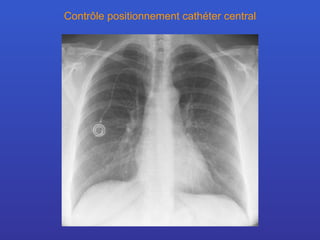

Contrôle positionnement cathéter central